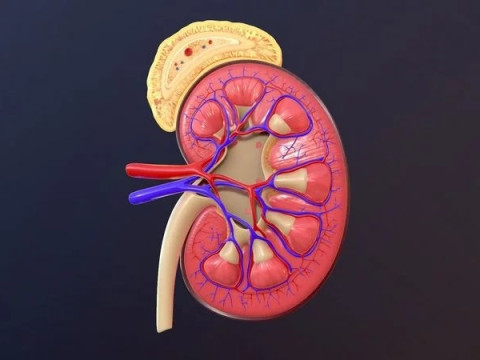

Human Kidney Low-poly Modelo 3D

Human Kidney Modelo 3D blend, jpg, fbx, max, De jack2024

human kidney renal urine organ anatomical health people anatomy biology urinary system electrolytes internal organs science medical crossNo hay comentarios sobre este artículo.